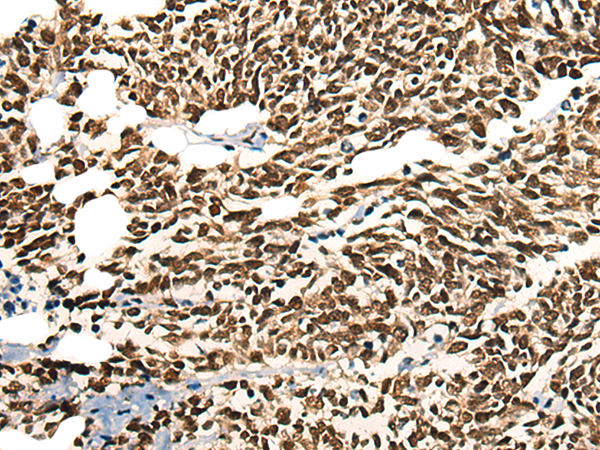

IHC 1/25-1/100 Human,Mouse,Rat

**摘要**:该研究通过免疫组化(IHC)和Western blot分析,发现MORF4L2在肺癌组织中表达降低,其缺失通过抗体检测关联于患者预后不良及肿瘤侵袭性增强。

The antibody is primarily utilized in research to detect MORF4L2 expression in tissues or cells via techniques like Western blotting, immunohistochemistry (IHC), or immunofluorescence (IF). It helps investigate MORF4L2's functional interactions, particularly its role in transcriptional coactivation with nuclear receptors and other transcription factors. Dysregulation of MORF4L2 is associated with acute myeloid leukemia (AML), colorectal cancer, and Rubinstein-Taybi syndrome, making the antibody valuable for studying disease mechanisms.